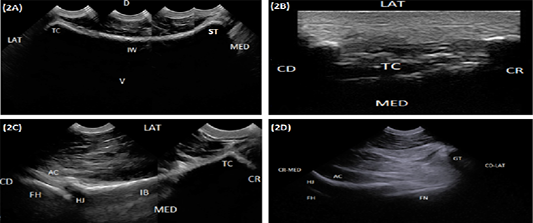

(A) Compound longitudinal sonogram (6.6 MHz micro convex probe, 10 cm depth) in a 5-year-old cow showing iliac wing (IW), sacral tuber (ST), tuber coxae (TC), lateral direction (LAT), medial direction (MED), dorsal direction (D) and ventral direction (V). (B) Longitudinal sonogram (10 MHz linear tendon probe, 5cm depth) in an 8-year-old cow showing tuber coxae (TC) lateral direction (LAT), medial direction (MED), cranial direction (CR) and caudal direction (CD). (C) Compound longitudinal sonogram (6.6 MHz micro convex probe, 10 cm depth) in a 5-year-old cow showing the iliac body (IB), hip joint (HJ), tuber coxae (TC), acetabulum (AC), femoral head (FH), lateral direction (LAT), medial direction (MED), cranial direction (CR) and caudal direction (CD). (D) Oblique sonogram (6.6 MHz micro convex probe, 15 cm depth) in an 8-year-old cow showing the hip joint (HJ), the acetabulum (AC), femoral head (FH), femoral neck (FN), greater trochanter (GT), craniomedial direction (CR-MED), and caudolateral direction (CD-LAT).